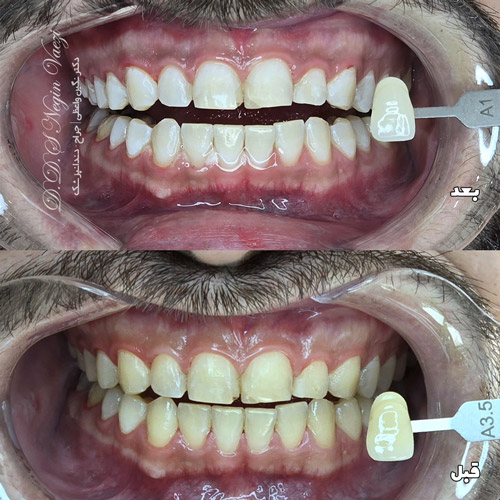

بلیچینگ چند درجه دندانها را سفید میکند؟ در واقعیت بالینی (با shade guide) بیشتر بیماران بین ۱ تا حداکثر ۴ درجه تغییر رنگ را تجربه میکنند. یعنی اگر دندان شما در ابتدا رنگ A3 باشد، ممکن است بعد از بلیچینگ به A1 یا حتی B1 نزدیک شود. بعنوان مثال در تصویر نمونه کار زیر تغییر رنگ تقریبا از A3.5 به A1 برابر با تقریبا 2.5 درجه تغییر یافته است.

همانطور که در نمونه کارهای فوق مشاهده می کنید عموما 2 الی 3 درجه تغییر رنگ در بیشتر افراد مشاهده می شود و در موارد نادر حتی بیش از 3 درجه نیز وجود دارد. در عین حال در برخی کیس های نادر نیز میزان تغییر رنگ کمتر نیز می باشد. که بستگی به نوع رنگ، جنس دندان ها و موارد مشابه دارد.لذا قبل از بلیچینگ حتما باید از نزدیک دندان ها معاینه شود. تا در صورت نیاز از روش های جایگزین بلیچینگ دندان برای بهبود زیبایی استفاده گردد.